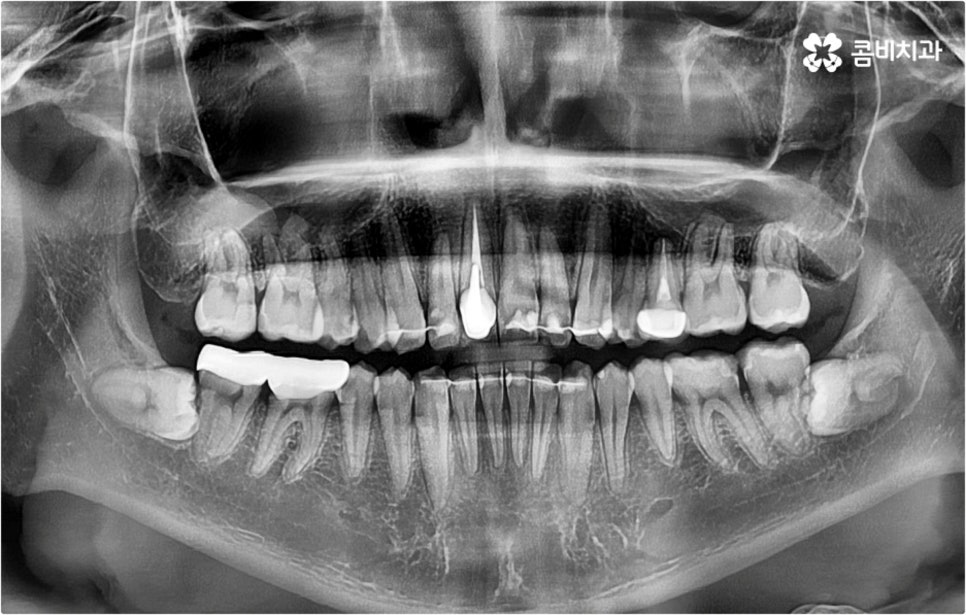

덧니교정 시 환자분들의 상황에 따라 치아 이동에 필요한 공간이 부족하지 않다면 비발치 교정이 가능한데요, 이런 경우 치아 사이를 살짝 갈아서 여유 공간을 만드는 치간 삭제 방법, 마지막 어금니를 후방으로 이동시키는 방법, 그리고 악궁 확장 장치를 사용해 치아 사이를 벌려주는 방법 등 다양한 방법으로 공간을 만들어 치열을 가지런하게 바로잡아 줄 수 있습니다. 이때 환자분들의 구강 상태, 즉 악궁 크기 대비 치아의 크기, 치아가 겹친 정도, 덧니의 위치와 개수 등을 자세하게 검진한 다음 치아가 이동할 충분한 공간이 확보되지 않는다면 발치 교정을 하게 될 거예요.

아마도 많은 분들이 치아를 뽑는다는 것에 대한 두려움을 가지고 있으시겠지만 그렇다고 해서 발치 교정이 필요한 케이스임에도 불구하고 치아를 뽑지 않고 진행을 하게 되면 치아 이동이 생각했던 것만큼 이루어지지 않기 때문에 결과에 따른 만족감이 떨어질 수 있어요. 특히 부정교합의 정도가 심각하고 골격적인 원인이 영향을 주고 있는 경우에는 발치 과정이 불가피 할 수 있으므로 의료진과 충분하게 상담을 하셔서 자신의 현재 상황에 따른 발치 교정의 필요성을 정확하게 이해하고 치료를 받으시길 권유드리고 있습니다.

오히려 경우에 따라 무리하게 발치를 할 경우 혹시 모를 부작용, 즉 너무 많은 치아 이동으로 인해 입이 들어가 보이는 합죽이 같은 결과로 이어질 수 있어 주의하실 필요가 있어요. 특히 환자분들 각자에게 맞는 치료 계획을 세울 때 구강 구조, 교합, 상하악 골격 등 기능적인 부분과 함께 연령별 특성에 따른 골밀도나 발달 상황 등을 전체적으로 고려하지 않고 일부만 선택적으로 개선하려고 하면 추후 턱관절과 저작력에 계속 문제가 생길 수 있으며 잇몸 상태를 고려하지 않은 채 무리한 진행을 하게 되면 치아와 잇몸 건강에 좋지 않은 영향을 줄 수 있기 때문에 교정 치료는 의료진의 섬세한 기술력을 요하는 복잡한 고난도 진료라고 할 수 있습니다. 임상 경험이 풍부하고 다양한 케이스에 대한 노하우를 가지고 있는 숙련된 담당의 선생님과 함께 하는 것이 굉장히 중요한 포인트인 거예요.